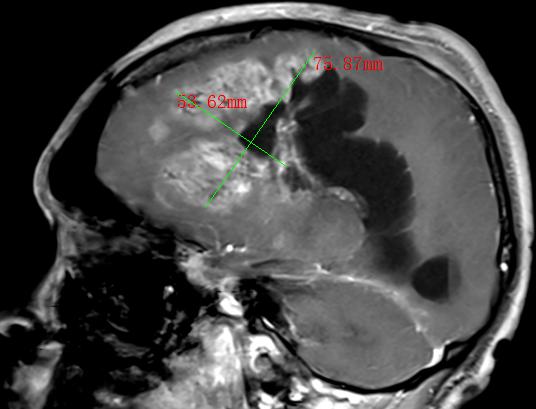

2022年,30多岁的张先生和40岁岁的李先生,均出现神志模糊或不清,并有反复癫痫发作的情况,经过当地医院检查,张先生和李先生分别诊断为松果体肿瘤、间变型星形细胞瘤术后复发并多发种植转移,两人颅内肿瘤直径分别达4.0cm和9.8cm。由于两人颅内肿瘤太大,辗转多家医院求医未果,正当两家人要放弃的时候,听朋友介绍瑞康医院射波刀治疗恶性肿瘤的效果非常不错,两家人怀着试一试的心态来到瑞康医院肿瘤科一区。

间变型星形细胞瘤术后复发并多发种植转移MRI影像